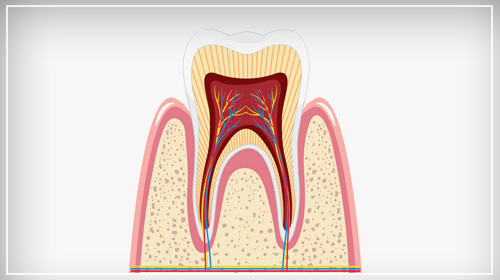

Advanced Root Canal Treatment

Root Canal Treatment or Endodontic Treatment in Dental Care Services becomes a necessity when a tooth becomes infected or inflamed, resulting in the infection of blood vessels, nerves, and connective tissues. The main role of this procedure is to save the injured tooth instead of being extracted. Health Square is one of the best Dental Clinics in Jaipur providing single-visit RCTs and RCTs with an endomotor.